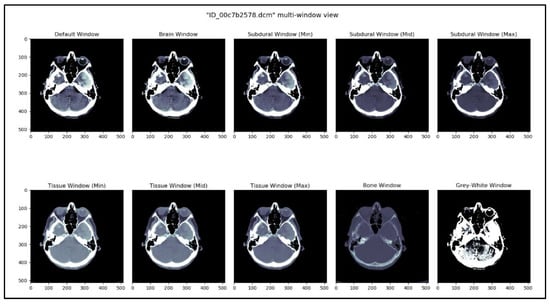

The kernel See like a Radiologist with Systematic Windowing [33] by David Tang discusses viewing DICOM files under various window settings before making a prognosis. This is the same strategy that radiologists utilize when reviewing CT scans in real-world scenarios. DICOM files vary depending on the window settings; certain hemorrhages are considerably simpler to identify under certain window settings. Windowing is used specifically for this purpose, reported in Table 4. Based on this kernel and our understanding of the process, ten window settings were chosen.

This methodology creates a temporal sequence. All window settings mentioned in Table 2 are applied, and the result is stacked. Figure 3 shows 10 different views of the DICOM image using different window settings. Figure 4 shows the creation of a temporal series taken as input by CNN. CNN extracts the spatiotemporal data and identifies the significant features. Later, the LSTM model utilizes the CNN model’s output and performs the accurate prediction level in the CT scan.

Figure 3. DICOM image viewed in 10 different window settings.